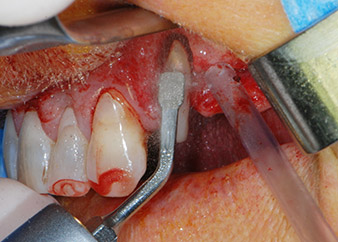

Antes de la colocación del implante y tras la verificación de que la membrana de Schneider estaba intacta (figura 9), la base interna del seno se aumentó en las dos posiciones del implante con un material sustituto de hueso xenógeno (Bio-Oss, Geistlich Biomaterials) (figura 10).

Fig. 9: Después de preparar el lecho del implante en la posición 26, la integridad de la membrana del seno se comprobó con una sonda periodontal CPITN con punta esférica.

sonda-CPITN

Fig. 10: Se insertó un material sustituto de hueso xenógeno en la osteotomía del implante para el aumento interno del seno. El material se condensó con cuidado en dirección apical con la sonda CPITN con punta esférica (no mostrado).